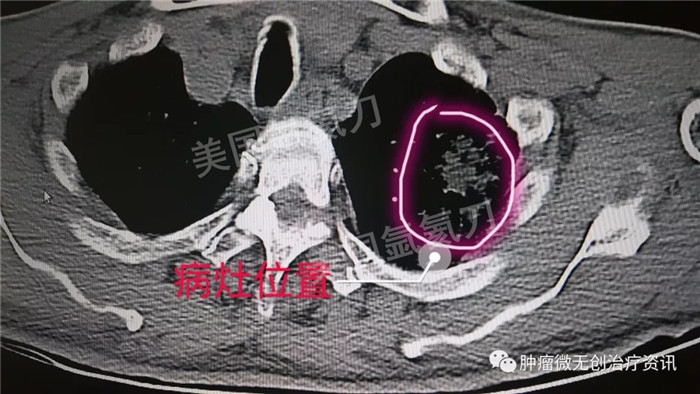

民航总医院氩氦刀冷冻消融治疗肺癌

63岁男性患者,发现左肺占位1天入院,伴多发骨转移及肺内转移,行氩氦靶向治疗减瘤,同时穿刺取病理活检。